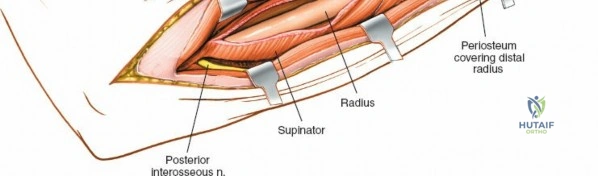

The proximal radius is draped by the supinator muscle. The PIN passes directly through the belly of the supinator. To protect the nerve, the forearm must be fully supinated. Supination dynamically rotates the radius, carrying the insertion of the supinator anteriorly and simultaneously displacing the PIN laterally and posteriorly, safely away from the surgical field.

With the forearm fully supinated, identify the broad insertion of the supinator on the anterior aspect of the radius. Incise the supinator directly along the line of its insertion onto the bone. It is critical to detach the muscle by dividing its insertion sharply at the bone, rather than splitting the muscle belly, which would risk cutting the PIN.

Proceed with strict subperiosteal dissection, elevating the supinator laterally off the bone. This is one of the rare instances in orthopedic surgery where the safety gained by staying in a subperiosteal plane completely outweighs the theoretical vascular damage to the bone caused by periosteal stripping. The elevated supinator muscle belly now acts as a protective cushion for the PIN.

Once the proximal radius is exposed, great care must be taken with retractor placement. Never place Hohmann or levering retractors blindly around the posterior surface of the radial neck. Because the PIN may touch the bone posteriorly in up to 25% of patients, a posteriorly placed retractor can easily crush the nerve against the radial cortex. Instead, use gentle right-angle retractors or place retractors only on the anterior and lateral aspects of the bone, utilizing the elevated supinator as a shield.